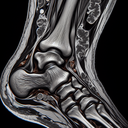

МРТ гомілково-ступневогу суглобу

Магнітно-резонансна томографія (МРТ) гомілково-ступневого суглоба – це неінвазивний метод візуалізації, який використовують для отримання детальних зображень тканин суглоба. МРТ допомагає виявити різні патології, такі як зв'язкові пошкодження, ушкодження хряща, набряки, запалення або інфекції. **Процедура:** 1...